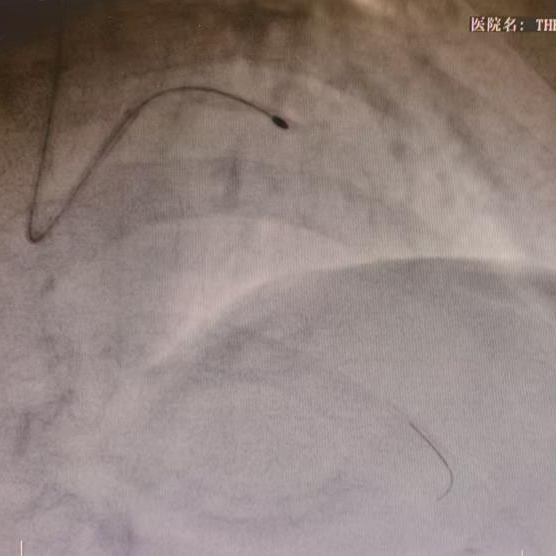

旋磨解决了“表面文章”,但血管壁深层的钙化环依然束缚着血管。团队随后使出了新利器——冲击波球囊技术。

冲击波球囊扩张病变

该技术犹如“隔山打牛”,在球囊低压扩张的状态下,通过发射高频声压力波,精准地“震裂”深层的钙化组织,而不会损伤柔软的血管壁。经过冲击波的处理,原本坚不可摧的血管恢复了应有的弹性。